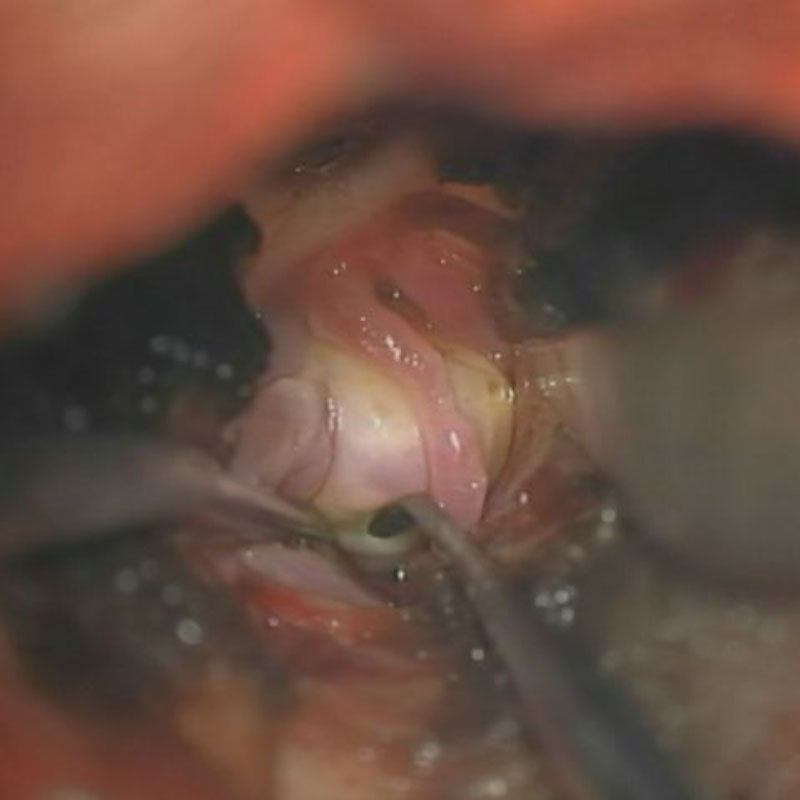

2

'26年1月

50代

右中大脳動脈瘤

クリッピング術

手術前

クリップ前

クリップ後

術後血管撮影